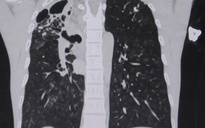

Tiếp theo, bệnh nhi được thực hiện chụp cắt lớp vi tính đa dãy (CT 512 lát cắt) mạch máu phổi, xác định dị dạng động - tĩnh mạch phổi (AVM) tại nhánh thùy dưới phổi phải, với đường kính lỗ rò khoảng 6,5 mm, chiều dài 20 mm, gây viêm vùng phổi.

Ê kíp can thiệp, bao gồm các bác sĩ chuyên khoa đột quỵ - can thiệp, nhi tim mạch - khớp, gây mê hồi sức cùng đội ngũ kỹ thuật viên, đã tiến hành thủ thuật gây mê nội khí quản. Qua tiếp cận tĩnh mạch đùi, bác sĩ thực hiện chụp mạch, xác định vị trí rò động - tĩnh mạch phổi lưu lượng cao. Sau đó, sử dụng ống thông chuyên dụng để bít lỗ rò bằng coil kết hợp onyx dưới màn huỳnh quang tăng sáng (DSA).

Kết quả chụp mạch sau can thiệp cho thấy lỗ dò đã được bít hoàn toàn. Độ bão hòa oxy máu của bệnh nhi tăng lên rõ rệt, đạt 96%, các chỉ số sinh tồn ổn định. Sau thủ thuật, bệnh nhi được rút nội khí quản và chuyển về Khoa nhi tim mạch - khớp để theo dõi.